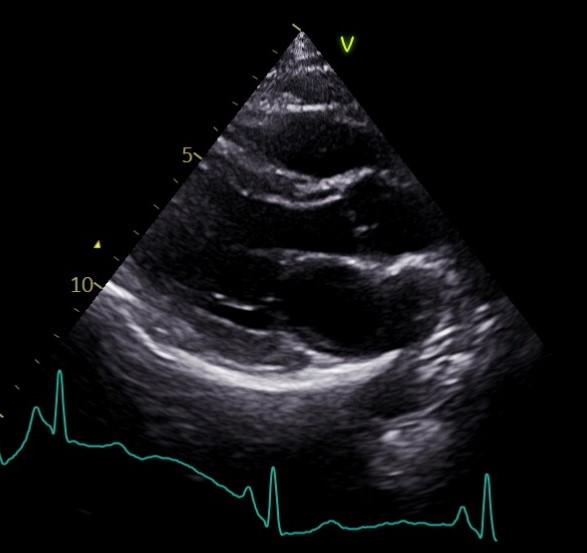

Image – Echocardiogram (Parasternal long axis view)